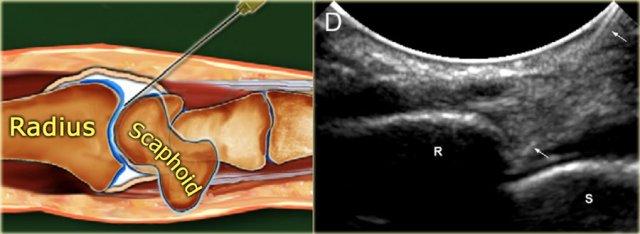

Radiocarpal joint

Bệnh nhân nằm ngửa với cổ tay gấp lại và đặt trên miếng bọt biển 45◦ hoặc một chiếc khăn cuộn lại.

Trong một số trường hợp, việc giữ cổ tay ở tư thế lệch trụ có thể giúp mở rộng khoang khớp hơn nữa.

Khoảng cách giữa xương quay và xương thuyền được xác định trên siêu âm.

Một kim 23-25 gauge, dài 30 mm được đưa vào khớp dưới hướng dẫn của siêu âm, hướng về phía bề mặt khớp của xương quay cho đến khi cảm nhận được sự tiếp xúc với xương quay.

Sau khi đảm bảo rằng đầu kim không nằm trong sụn xuyên tâm, tiến hành bơm 2-4 mL thuốc cản quang.

Vát của kim hướng về phía khoang khớp và thuốc cản quang được thấy chảy vào trong khớp.